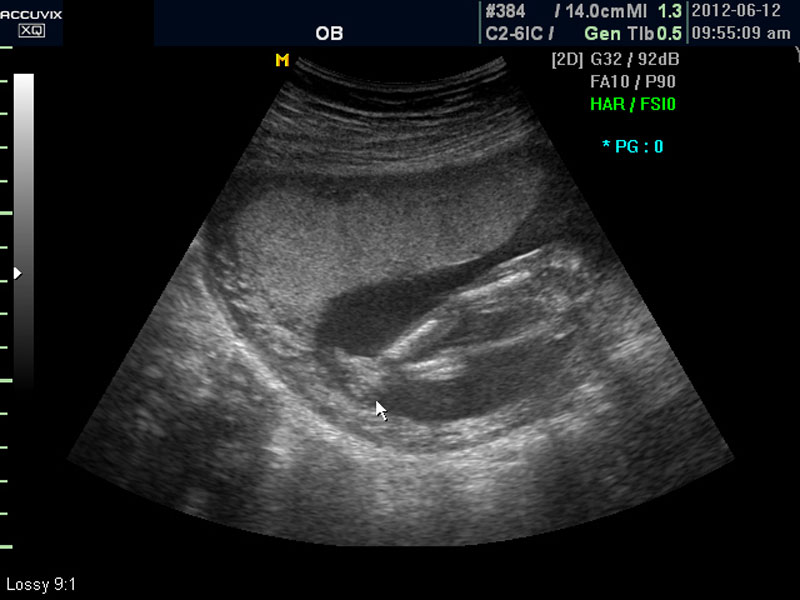

위 사진은 태아의 발바닥 사진인데 사진에서 보는 것처럼 그러나 이 시기는 손가락이나 발가락 또는  심장 내부의 구성 이상 등의 세세한 부분은 아직 크기가 작아서 제대로 확인하기 어려운 시기입니다.

대신 첫번째 사진에서 보는 것처럼 태아의 전체 모습 특히 태아의 등쪽이나 복벽의 이상은 없는지 신경관 결손 등으로 인한 종괴가 있지는 않은지 관찰하며 태아의 복벽이나 등쪽은 일직선으로 매끈하게 보이는 것이 정상입니다.

첫번째 사진에서는 하지 부분은 대퇴부만 일부 보이며 이는 태아가 다리를 구부리고 있고 팔도 이리저리 움직여 머리 위나 목 쪽으로 두는 경우가 많아서 한번에 전체 모습을 찍기가 어려운 경우가 많습니다.

따라서 부분 부분 살펴 보면서 해당 모습을 찍어서 저장하거나 인쇄하여 드리기도 하는 것이며 아래 사진은 태아의 다리 부분을 찍은 것입니다.